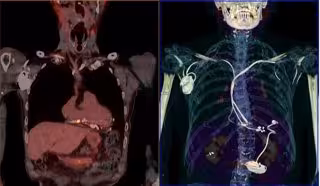

Image de archivo de un estudio PET-TC.

Image de archivo de un estudio PET-TC. - SEMNIM